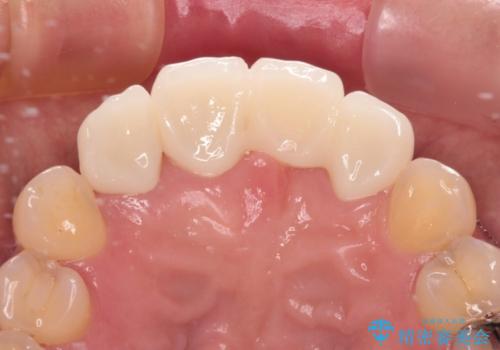

中途半端な矯正治療と前歯の欠損 再矯正とオールセラミッククラウンによる補綴治療

矯正治療により前歯横幅のバランスを整えた後に、上顎前歯をオールセラミックブリッジにて補綴治療を行うこととしました。